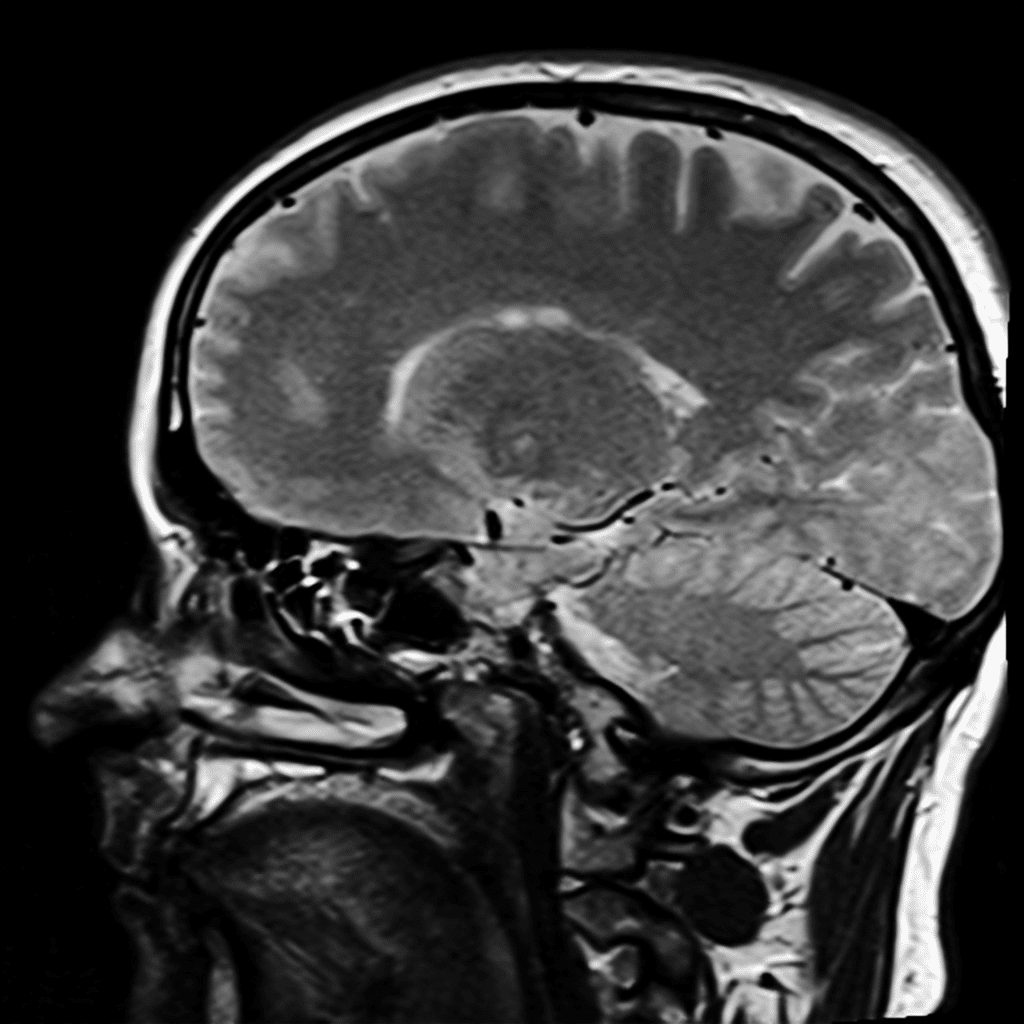

Un nuovo sistema di intelligenza artificiale (IA) sviluppato dall’Università del Michigan è in grado di analizzare le risonanze magnetiche (MRI) del cervello e fornire una diagnosi nel giro di pochi secondi. Secondo uno studio pubblicato su Nature Biomedical Engineering, il modello ha raggiunto una precisione fino al 97,5% nell’identificazione di patologie neurologiche ed è anche capace di stabilire quanto sia urgente l’intervento medico per ciascun paziente.

Il sistema è stato battezzato Prima dal suo ideatore, il neurochirurgo Todd Hollon. Nel corso di un anno, il team di ricerca ha testato l’IA su oltre 30.000 studi di risonanza magnetica, confrontandone le prestazioni con quelle di altri modelli avanzati.

I risultati mostrano che Prima ha ottenuto prestazioni superiori in più di 50 diverse diagnosi radiologiche, che coprono molte delle principali patologie neurologiche. Ma non solo: l’IA è in grado anche di assegnare una priorità clinica ai casi, distinguendo quelli che richiedono un intervento immediato da quelli meno urgenti.

Dal punto di vista tecnico, Prima è un Vision Language Model (VLM), una categoria di IA in grado di elaborare contemporaneamente immagini, testo e dati contestuali. A differenza di molti sistemi precedenti, addestrati su dataset limitati e focalizzati su compiti specifici, Prima è stata istruita su un’enorme mole di dati reali.

Il team ha utilizzato tutte le risonanze magnetiche archiviate dall’Università del Michigan da quando i dati radiologici sono stati digitalizzati: oltre 200.000 studi MRI e 5,6 milioni di sequenze di imaging. A questi si aggiungono le storie cliniche dei pazienti e le motivazioni per cui i medici avevano richiesto l’esame.

In pratica, Prima non analizza solo le immagini, ma integra il contesto clinico, cercando di replicare il processo decisionale di un radiologo umano. Questo approccio consente al modello di essere più flessibile e più affidabile su una vasta gamma di scenari.